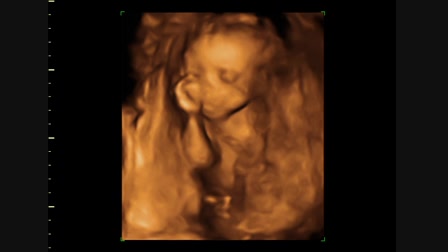

Hédi forog 2